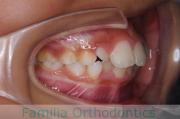

No.23V-132

- 主な症状:

- 開咬

- 年齢:

- 16歳

- 性別:

- 男性

- 抜歯部位

- 上:

- 88

- 下:

- 主な使用装置:

- FEA

- 治療にかかった費用:

- 87万円

開咬なので治療したいとのことで来院されました。受け口傾向のある開咬(前歯が咬み合わない)でしたので、下の親知らずを抜歯してマルチブラケット法にて治療を行いました。約1年半、20回程度の通院が必要でした。開咬は舌の癖の影響が強く、後戻りのリスクが高いケースといえます。